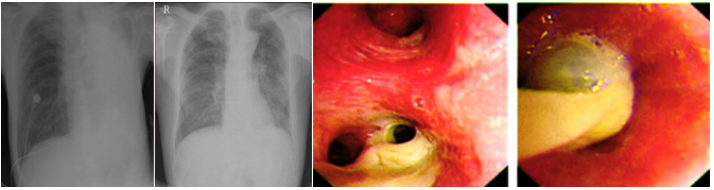

床旁支气管镜可以快速解除中心气道阻塞,适用于:①气道内异物,包括分泌物、积血以及其他异物(图1);②良性病变。例如感染、良性肿瘤或增生、气道支撑结构的破坏等(图2);③恶性病变,例如气道内肿瘤组织堵塞、气道壁浸润以及管腔外的压迫(图3)

图片

图1  支气管镜处理痰液阻塞

图2  支气管镜急诊处理良性气道狭窄

图3  食管癌侵犯气管致大气道狭窄—覆膜支架植入